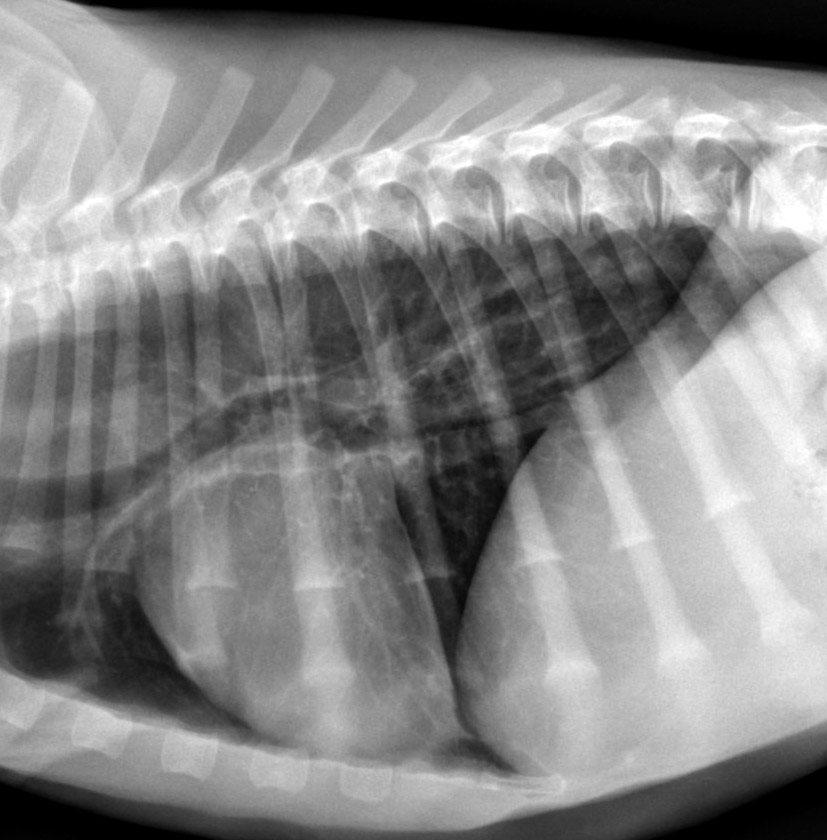

Diagnostic Imaging: Abdominal Distance

Education

1 September - 30 November 2025

100 CPD Points

Online Tutorials

Monthly

Tutor

Zoe Lenard

BVSc (Hons) FANZCVS (Radiology)

Early Bird

30 June 2025

Developanorderedandlogicalapproachto imagingandevaluationoftheabdomen.

Thiscoursecoversabdominalimagingwithradiography, ultrasonography,andCT,focusingondiagnosing diseasesincatsanddogs.Practitionersrefineskills throughcasestudies,quizzes,feedback,andanoptional reviewsection.

cve edu au/abdominal-imaging